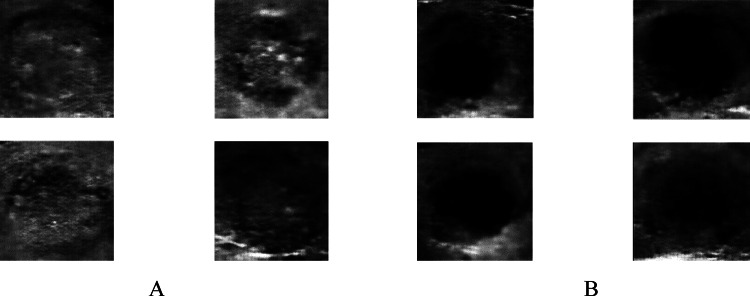

Fig. 7.

Quadruple view of 32 × 32 created class pictures in two separate classes A calcification mass B cystic gland and

After training the network for 26 min and repeating the learning process up to 15,000 times to understand 32 × 32 input images, the output shows improved clarity compared to 28 × 28 images. This finding aligns with the study by [7], which suggests that increasing the size of the input data can lead to better output images. By comparing Fig. 7 with Fig. 6, it becomes apparent that image size positively influences recognition and output quality.